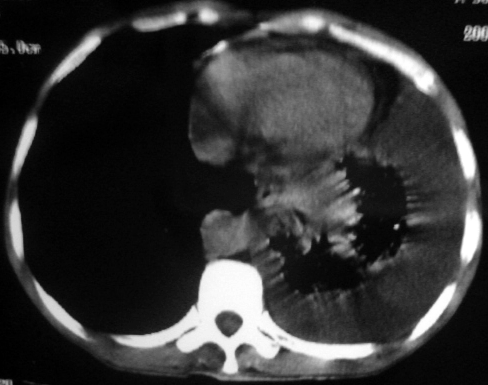

男,54岁,咳嗽,气喘半年,胸痛一月.

血性胸水

支持左肺下叶中心型肺癌(累及舌叶)伴阻塞性肺炎、膨胀不全、胸腔积液、心包少量积液。

左肺下叶中心型肺癌,伴阻塞性肺炎、左胸腔积液、心包少量积液。

1.左肺下叶中心性肺癌伴阻塞性肺炎,肺不张.

2.左侧胸腔积液,心包积液